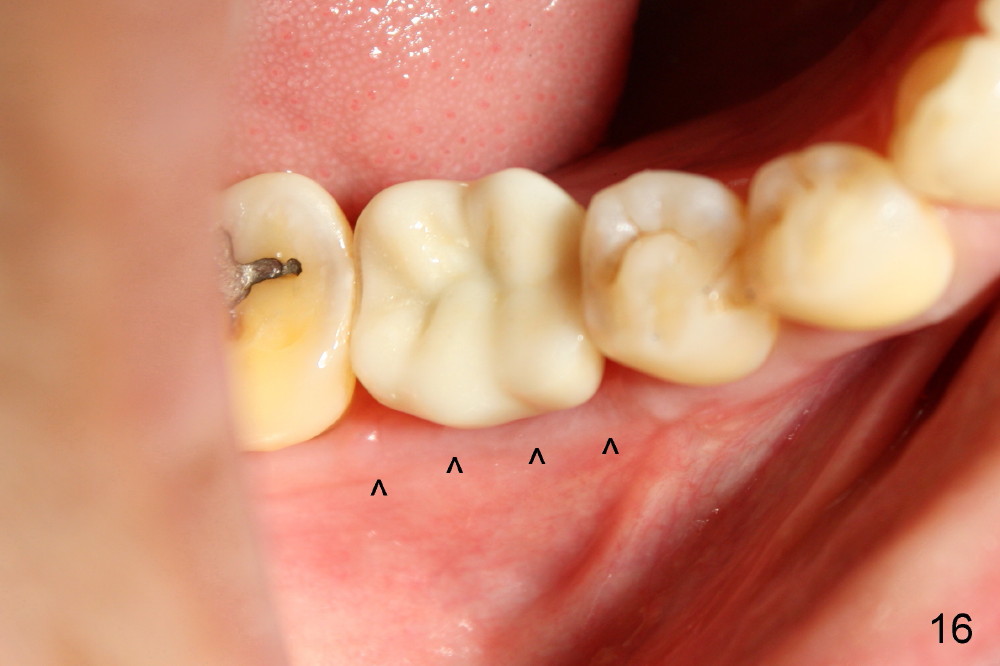

The infection is treated surgically. Nine months post-implantation, there is minimal buccal plate resorption (Fig.16 follow arrowheads). This is the most important reason of immediate implantation.